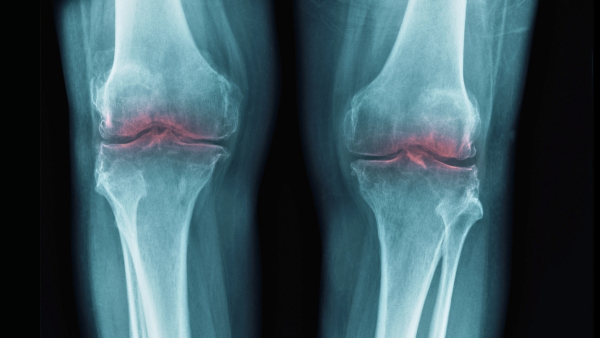

Μια μελέτη σε ποντίκια από ερευνητές του Πανεπιστημίου του Στάνφορντ ανίχνευσε την απώλεια χόνδρου που συνοδεύει τη γήρανση σε μία μόνο πρωτεΐνη, υποδεικνύοντας θεραπείες που μπορεί κάποια μέρα να αποκαταστήσουν την κινητικότητα και να μειώσουν την ενόχληση στους ηλικιωμένους, συμβάλλοντας με αυτόν τον τρόπο στην αντιμετώπιση της οστεοαρθρίτιδας.

Αυτό οδήγησε τους επιστήμονες να εξετάσουν εάν η 15-PGDH μπορεί να εμπλέκεται στην οστεοαρθρίτιδα, όπου η καταπόνηση στις αρθρώσεις οδηγεί στη διάσπαση του κολλαγόνου στον χόνδρο, προκαλώντας φλεγμονή και πόνο.

Εκτός από την αντικατάσταση των αρθρώσεων που επηρεάζονται, οι τρέχουσες επιλογές θεραπείας για την οστεοαρθρίτιδα περιορίζονται στη διαχείριση του πόνου. Παρά την πολλά υποσχόμενη έρευνα τα τελευταία χρόνια, δεν έχουμε ακόμη τίποτα που να αντιμετωπίζει την αιτία της πάθησης.